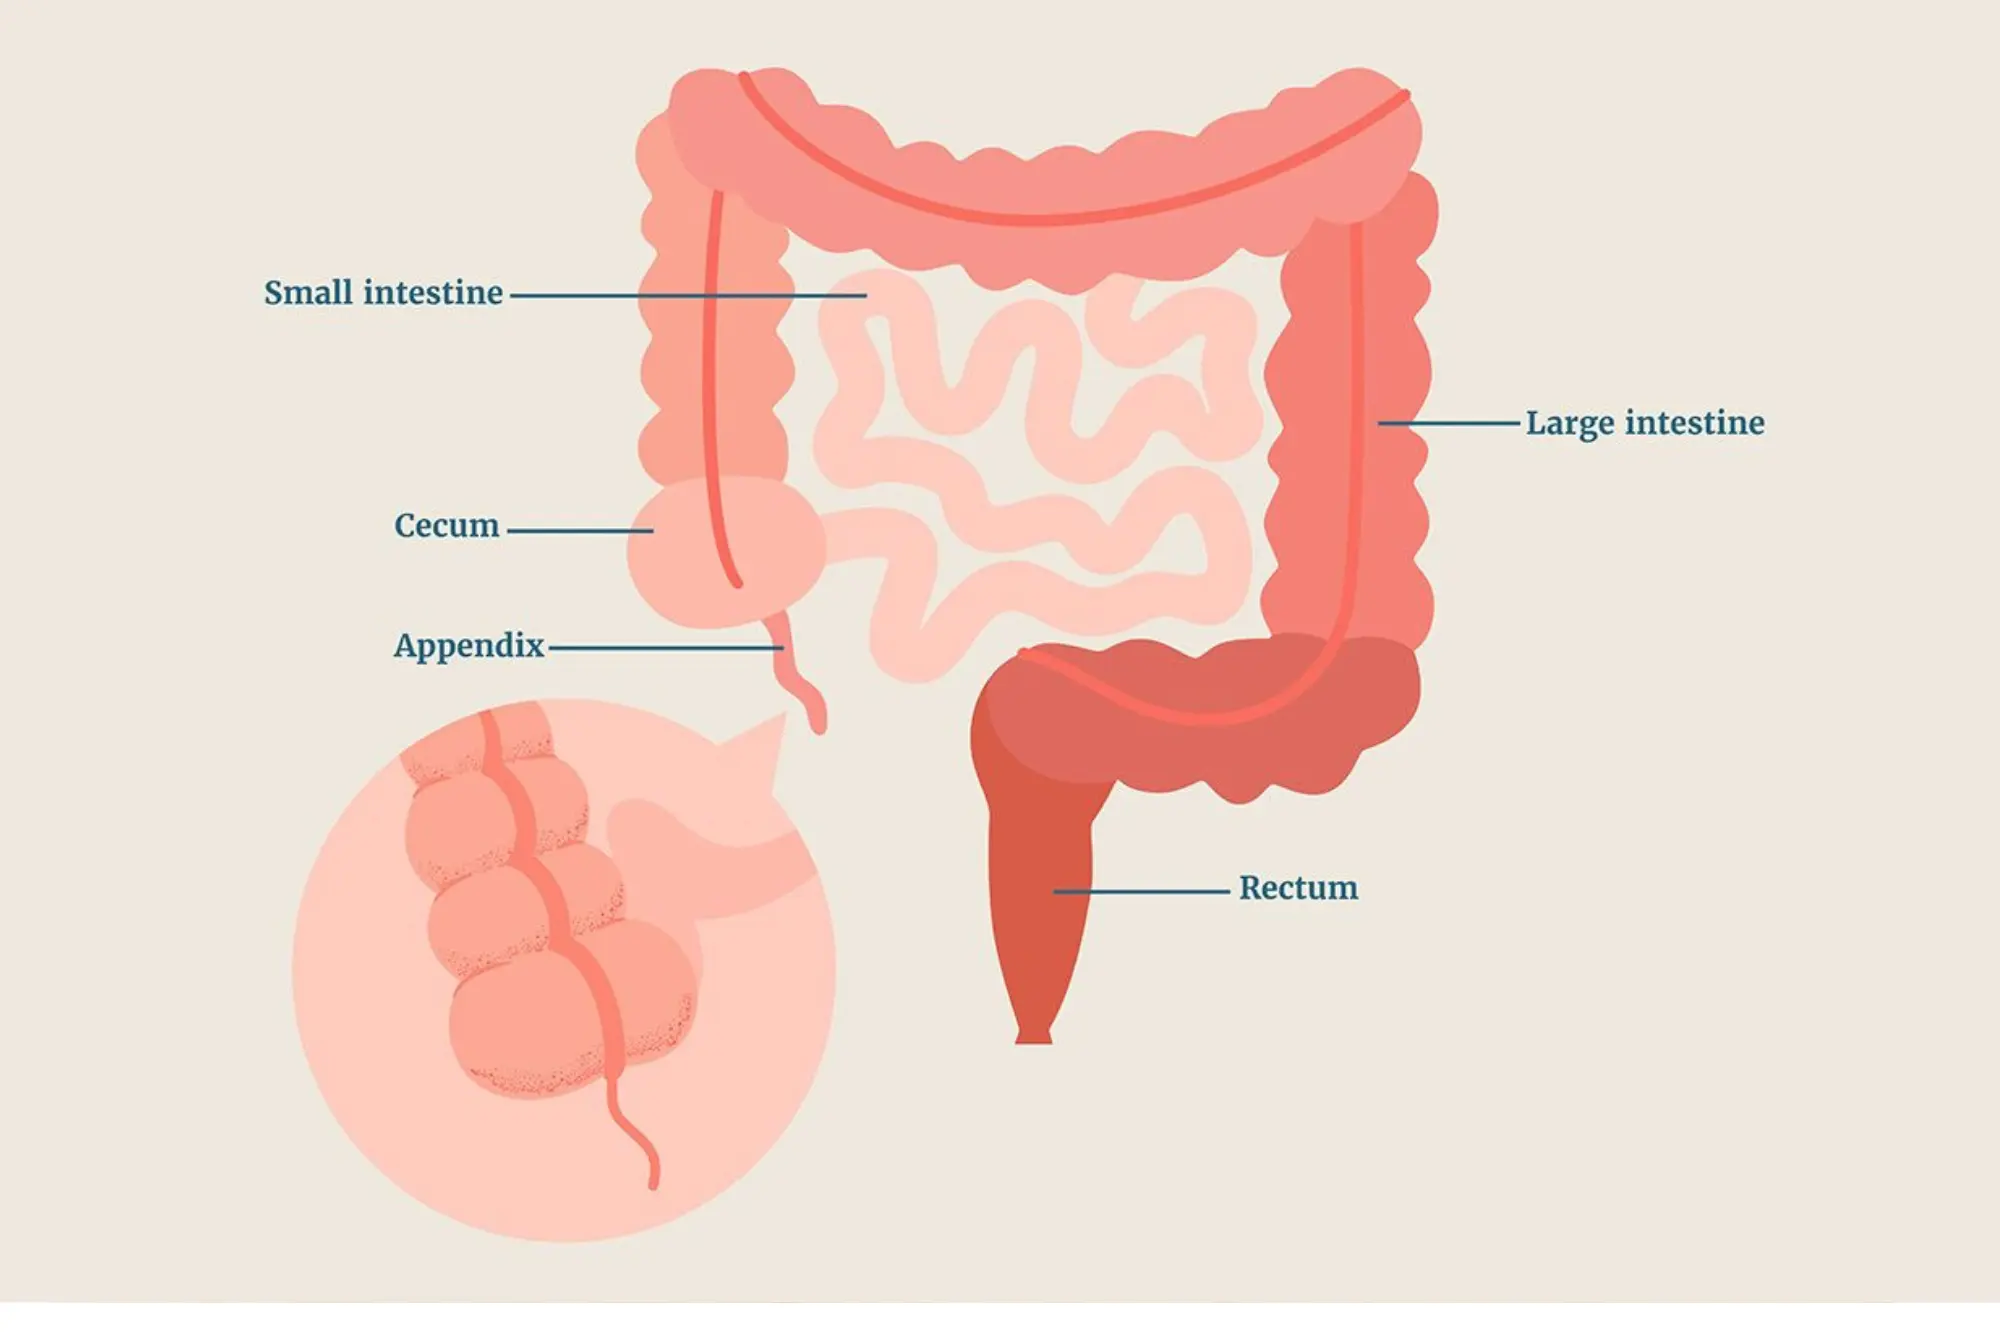

Appendicitis

Appendicitis is a medical emergency where the appendix becomes inflamed and filled with pus.